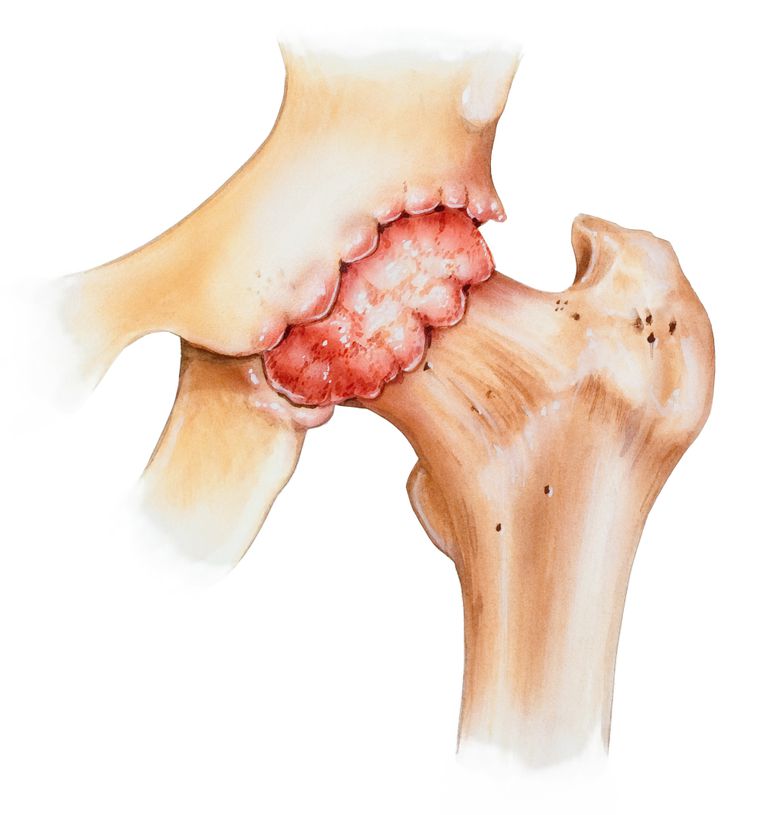

Костные наросты тазобедренного сустава

Причины образования остеофитов тазобедренного сустава:

- генетическая предрасположенность;

- отсутствие физической активности;

- травмы костей;

- лишний вес;

- воспалительные дегенеративные патологии (лечение будет наиболее сложным).

Частая причина остеофитов такого сустава — запущенная форма остеоартроза. На начальных этапах размер остеофитов не будет превышать 1-2 мм, однако наросты способны увеличиваться до 5 мм и приобретать заостренную форму.